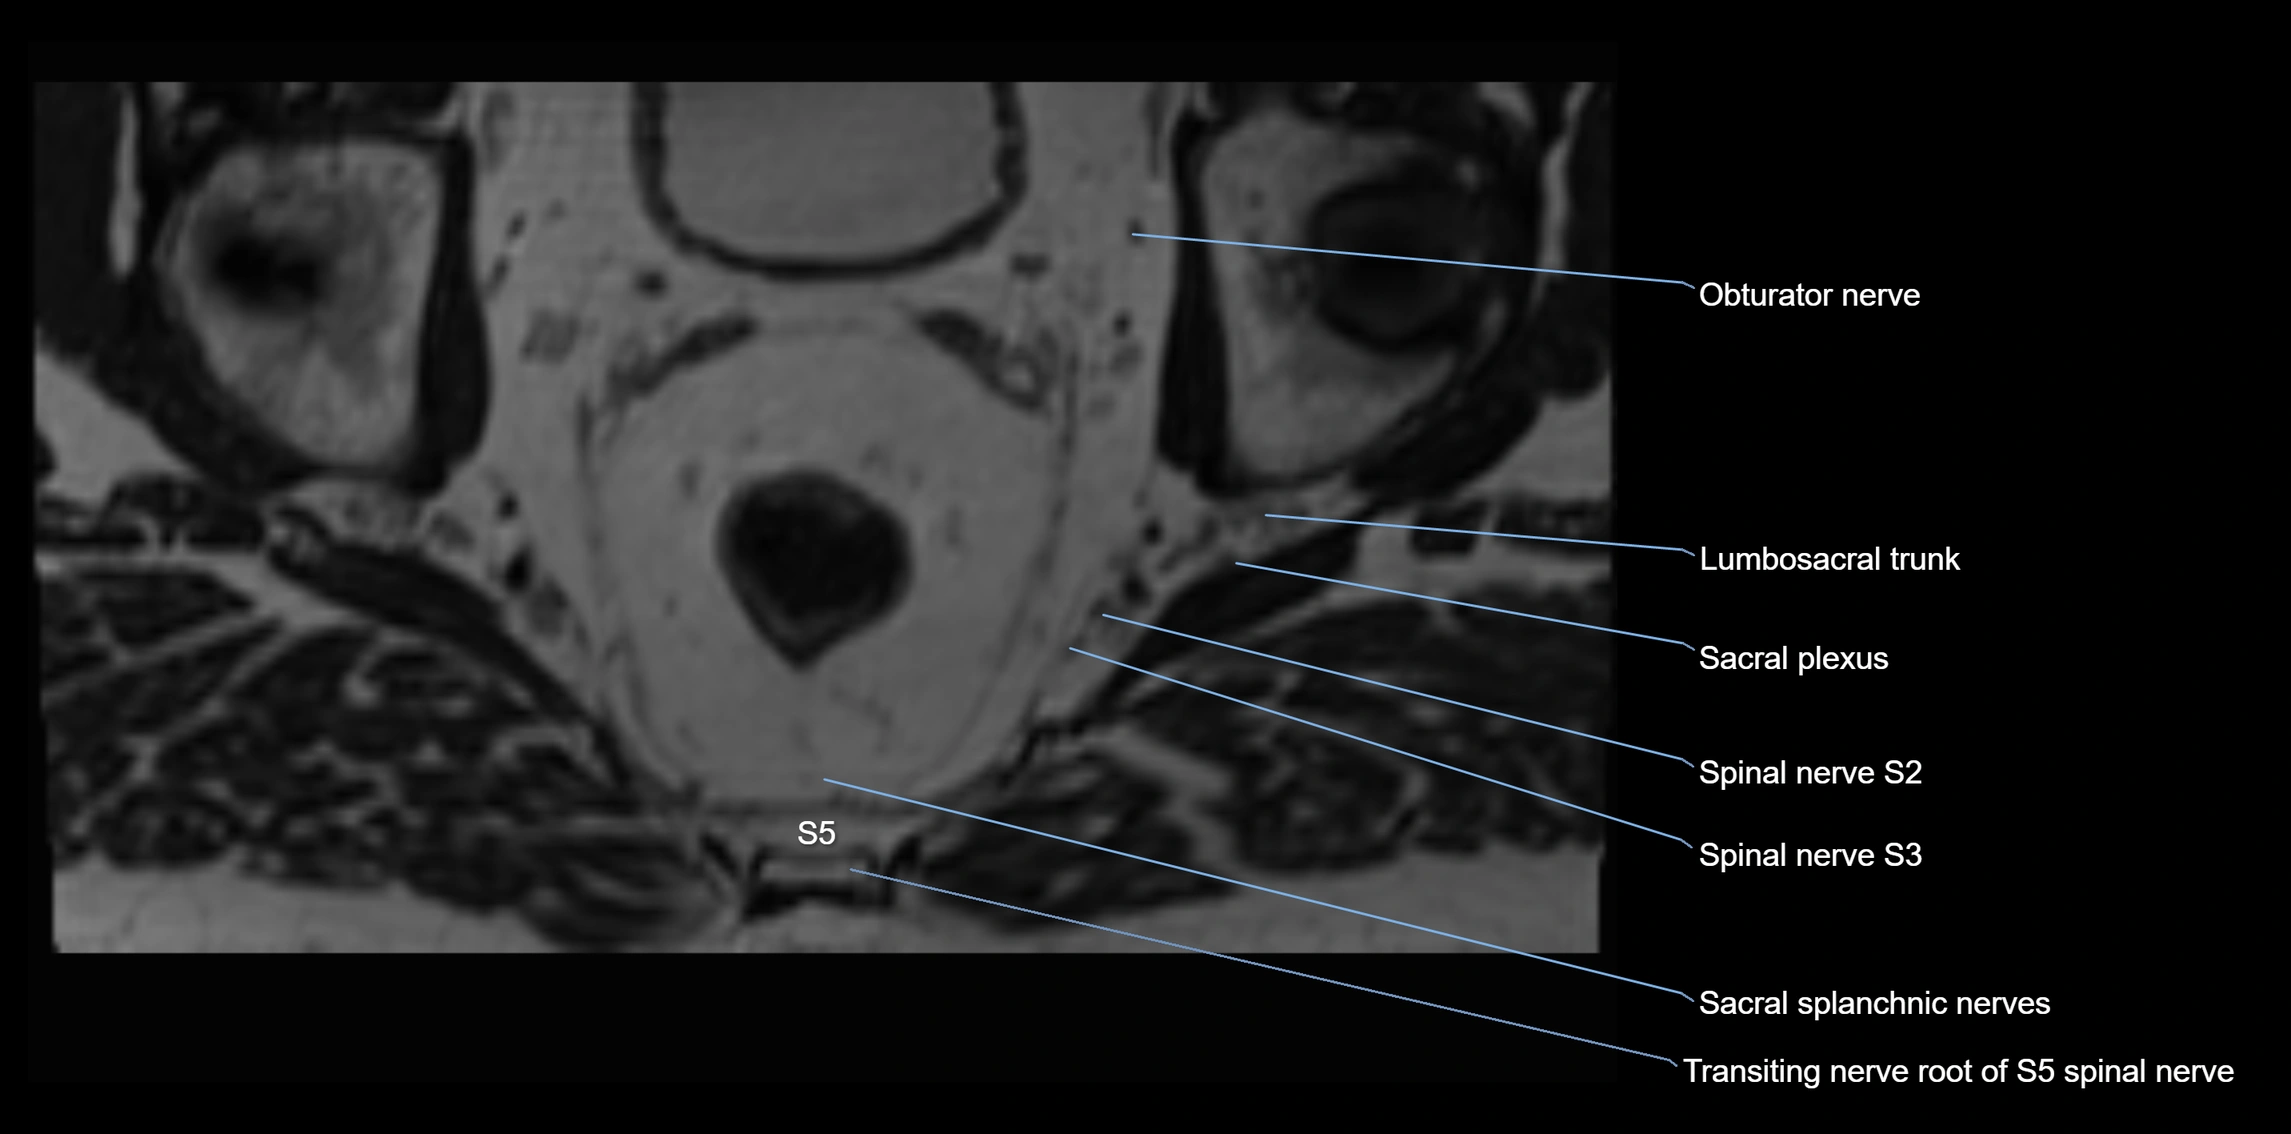

MRI image

image